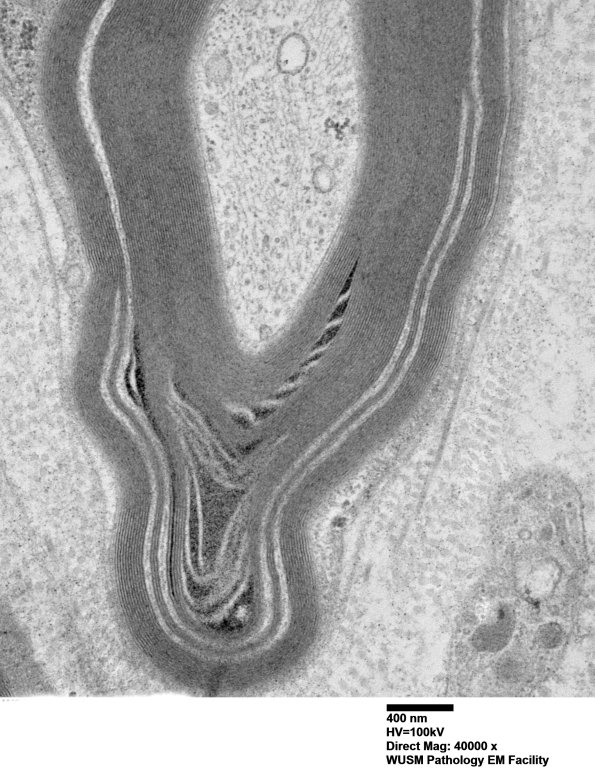

In this case there is an association of WSM and a Schmidt-Lanterman cleft. (electron micrographs)